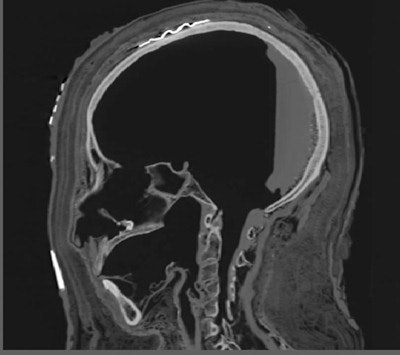

Using a 320-slice CT scanner (Aquilion One, Toshiba Medical Systems Europe), van Beek and colleagues performed 0.25 mm volumetric imaging using two kV settings and using maximal mAs. Additional imaging of the head was performed, using a gantry tilt to allow for better reconstruction of the head and facial bones.

Many hours of analysis followed. The radiology team spent a lot of time analyzing the images, working with forensic pathologist Dr. Elena Kranioti, lecturer in forensic anthropology at the University of Edinburgh and her anthropology team to perform measurements, study for potential cause of death or trauma, reconstruct the face, and clarify detailed information on findings discovered within the shroud.

The mummy was an Egyptian woman in her late 20s, according to Kranioti, who led the analysis of data to determine the mummy's age, sex, stature, health, and ethnicity. She was approximately 158 cm (62 inches) in height. She appeared to be healthy at the time of her death, the cause of which could not be determined. Her teeth were well maintained, with minimal tooth decay, which meant that she had been eating relatively refined foods that did not contain any sand.